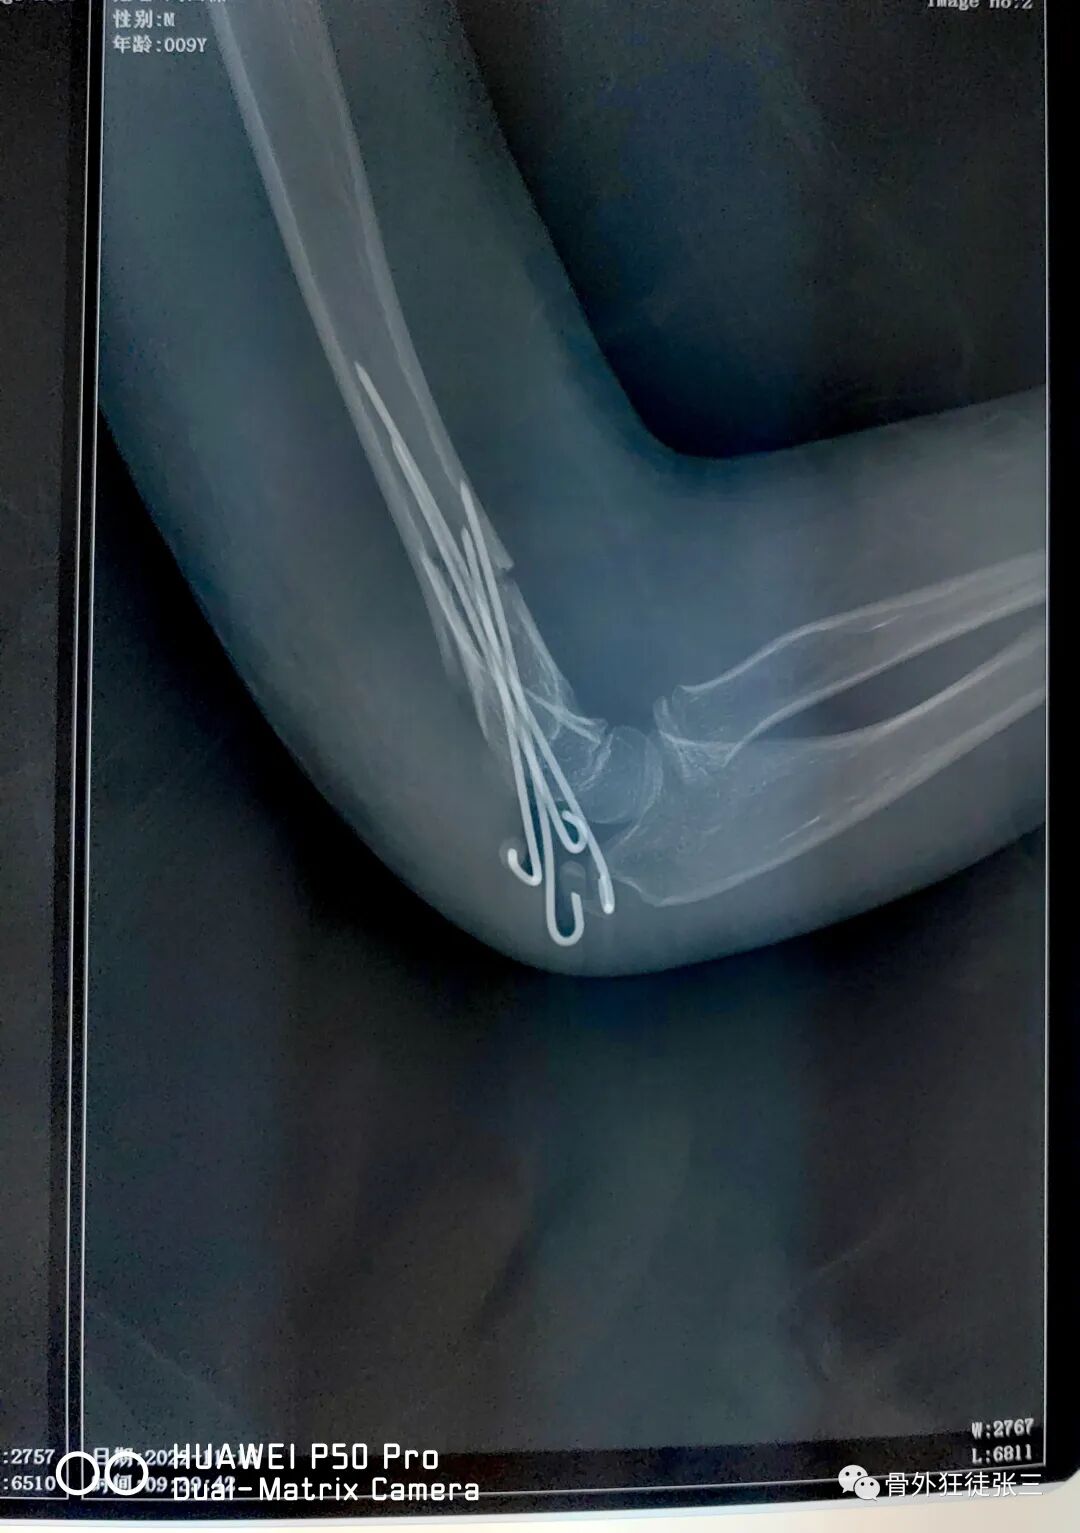

病例14,儿童髁上骨折零切开,桡侧三枚针发散固定

病例15,儿童髁上骨折零切开,

病例16,儿童髁上骨折零切开

病例17,低位髁上骨折零切开

病例24,低位髁上骨折零切开,闭合复位克氏针发散固定

病例25,开放性粉碎性指骨骨折,克氏针固定

病例31,儿童髁上骨折零切开,闭合复位克氏针

病例32,第345掌骨开放性骨折,克氏针髓内+克氏针支架

病例35,3型儿童髁上骨折零切开,闭合复位克氏针

病例38,儿童髁上骨折零切开,克氏针发散固定

病例46,尺骨鹰嘴骨折,克氏针张力带

病例52,高位髁上骨折零切开,闭合穿针

53,儿童髁上骨折零切开,交叉针